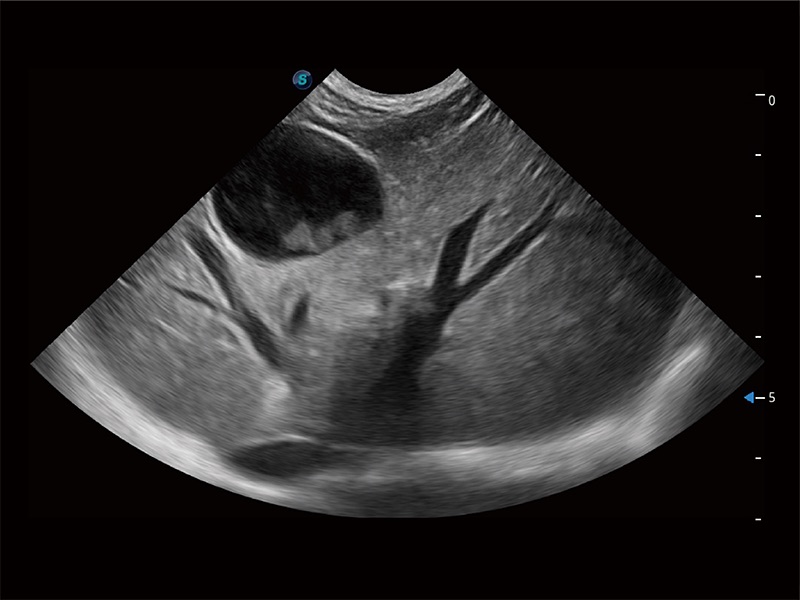

(犬)胎儿四腔心